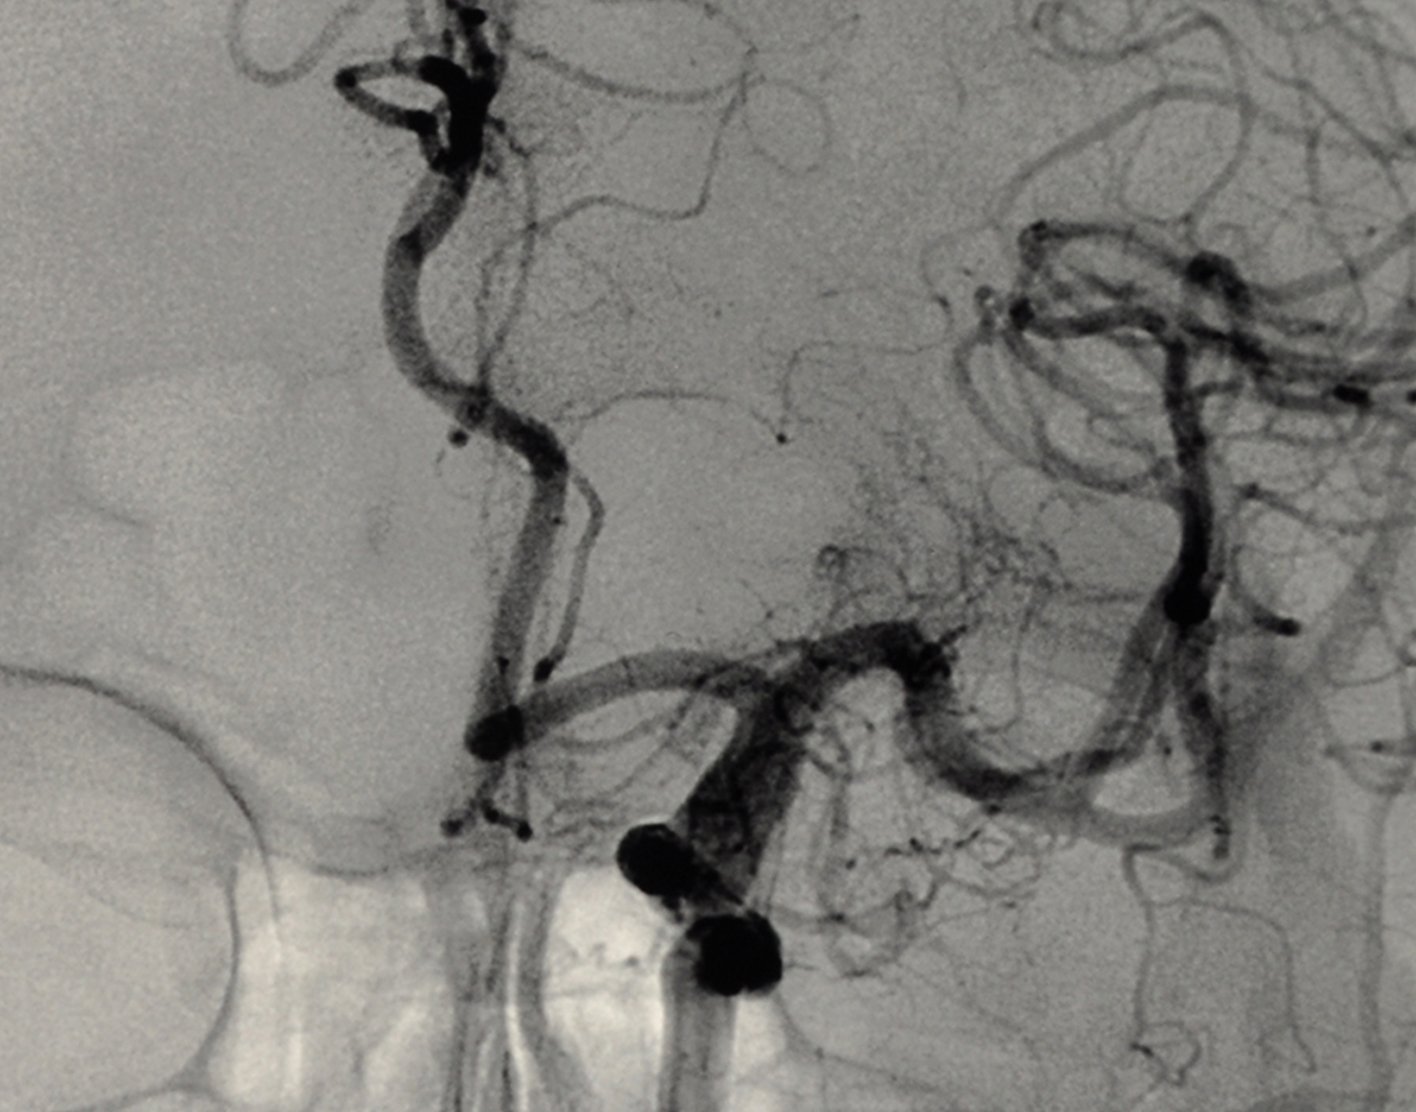

Cerebral angiography is a procedure that uses a special dye (contrast material) and x-rays to see how blood flows through the brain.

Once the catheter is in place, dye is sent through the catheter. X-ray images are taken to see how the dye moves through the artery and blood vessels of the brain. The dye helps highlight any blockages in blood flow.

Sometimes, a computer removes the bones and tissues on the images being viewed, so that only the blood vessels filled with the dye are seen. This is called digital subtraction angiography (DSA).